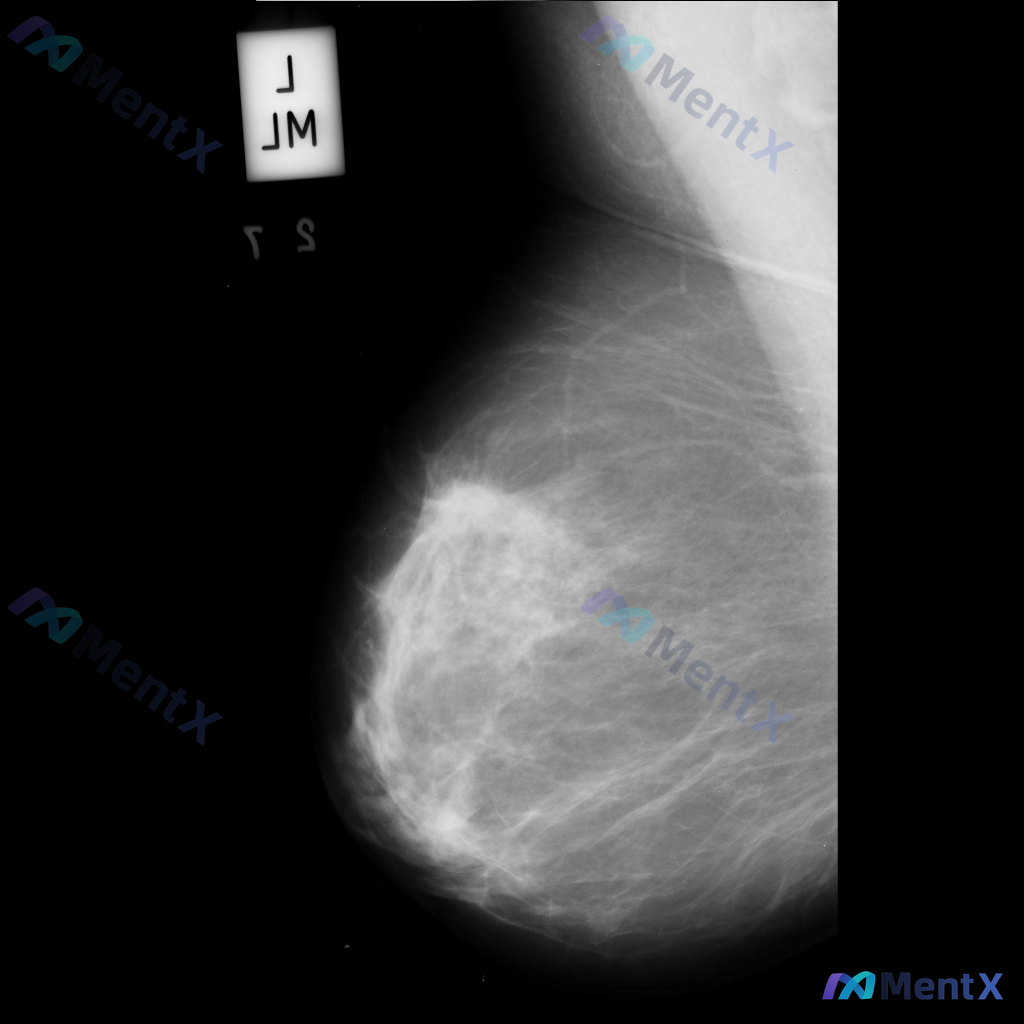

这张左乳钼靶影像,大家看核心异常更倾向哪种情况?

- 检查部位:左乳

- 投照体位:内外斜位(MLO)

- 左乳外侧偏上象限可见不规则高密度肿块影

- 肿块边缘模糊,部分区域有毛刺样改变

- 肿块周围存在局限性结构扭曲